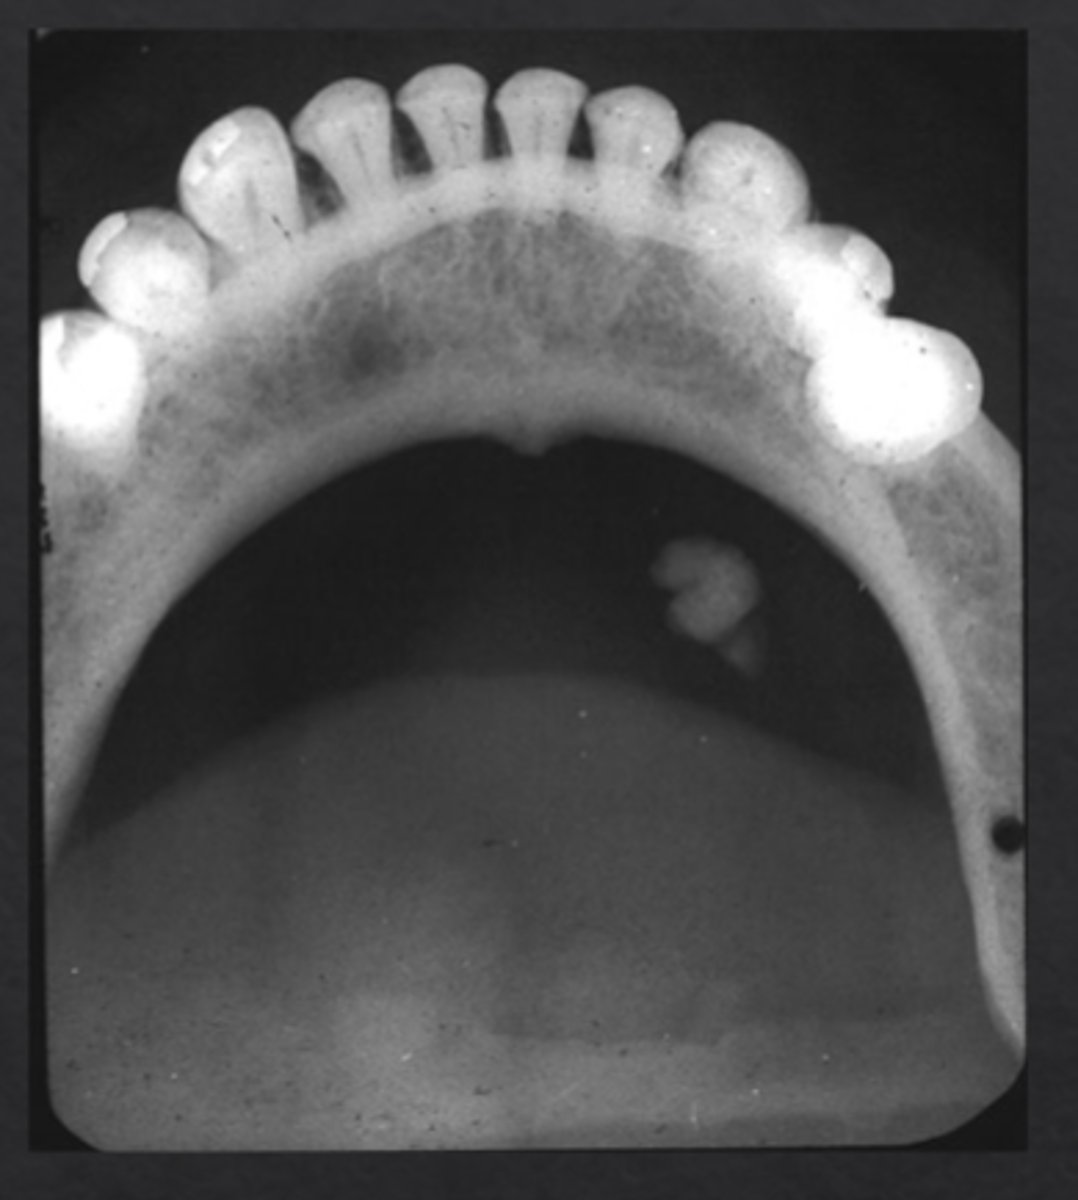

What is a mesiodens?

Supernumerary tooth between maxillary central incisors

What are supernumerary teeth?

Extra teeth beyond the normal dentition